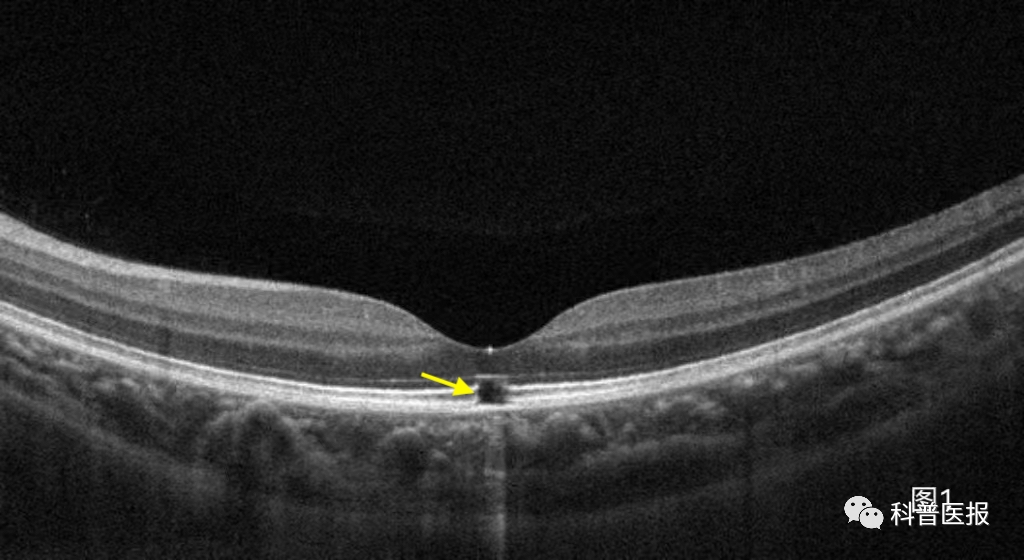

最近,我接诊了一个叫小温的12岁男孩,发现左眼视力下降,配眼镜时矫正视力只有0.7,所以被介绍到我诊室做进一步检查。详细询问小温情况后得知他除了左眼视物模糊,还伴有眼前中央固定白影遮挡,眼底OCT检查,可见黄斑中心外层组织部分缺损(图1)。详细追问病史得知,小温自己在路边摊偷偷买了激光笔,平时在学校和小朋友们相互照射玩耍,视力下降已有半年多,却一直没敢和父母说,最后小温确诊为左眼光损伤。看完这个小病人,不由得让我想起前一个月门诊还看过一个类似病情的小女孩,甚至一年前还有一个男孩因为激光笔损伤造成一眼黄斑裂孔后来做了手术(图2),遗憾的是术后视力也不能恢复。这些接二连三发生的事情,促使我想和小朋友和家长朋友们说点什么。

图1 激光笔照射后导致黄斑中心凹区外层缺失断裂(黄箭头)